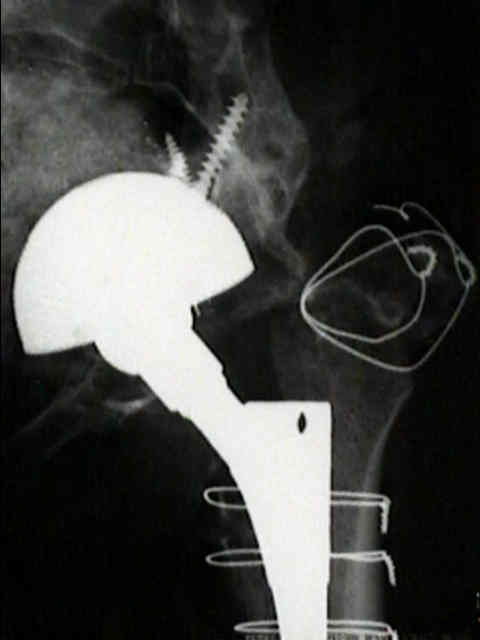

Loosening of Press Fit Acetabular Components

(press fit acetabular components)

radiographic signs of loosening

- radiolucent lines that initially appeared after two years

- progression of radiolucent lines after two years

- radiolucent lines in all three zones

- radiolucent lines 2 mm or wider in any zone

- migration

- loosening is present w/ more than 2 mm of migration (either horizontal or vertical);

- continuous radiolucent line;

- note that peripheral radiolucent lines which are non-continuous are commonly found in press fit acetabular components and are often not progressive;